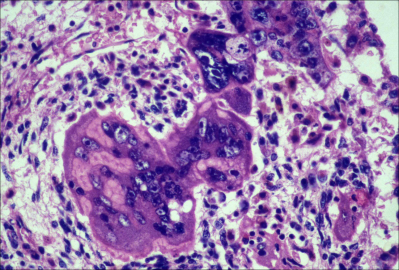

Choriocarcinoma

STGC = syncytiotrophoblastic giant cells